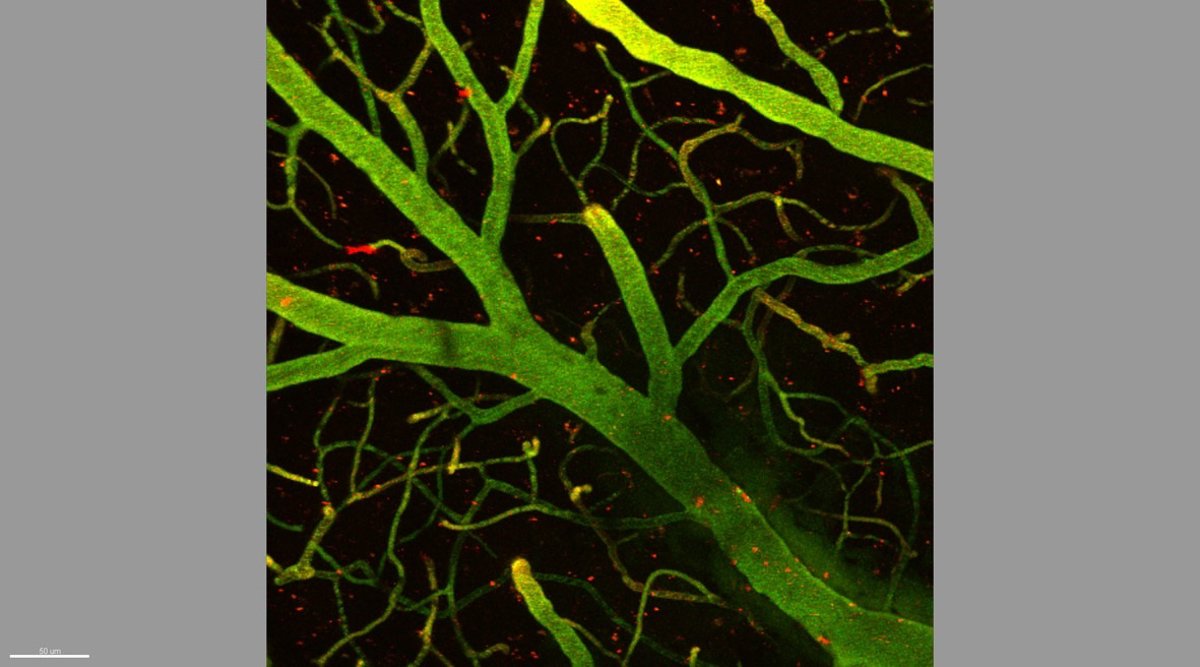

Según ha informado este jueves el IRB en un comunicado, una barrera de células controla el paso de sustancias de la sangre al cerebro para protegerlo: la función protectora es a su vez "un semáforo en rojo infranqueable" para el 98% de fármacos candidatos a tratar enfermedades del sistema nervioso central.

Esta barrera no es totalmente hermética porque el cerebro debe nutrirse constantemente de oxígeno, hierro e insulina, ha dicho Teixidó, y ha añadido que existen mecanismos de transporte "a modo de puertas que se abren y se cierran continuamente".

Aprovechando los receptores por los que el cerebro se abastece de hierro, el mecanismo ideado consigue pasar "sin entorpecer el paso de los nutrientes ni alterar la función protectora de la barrera".